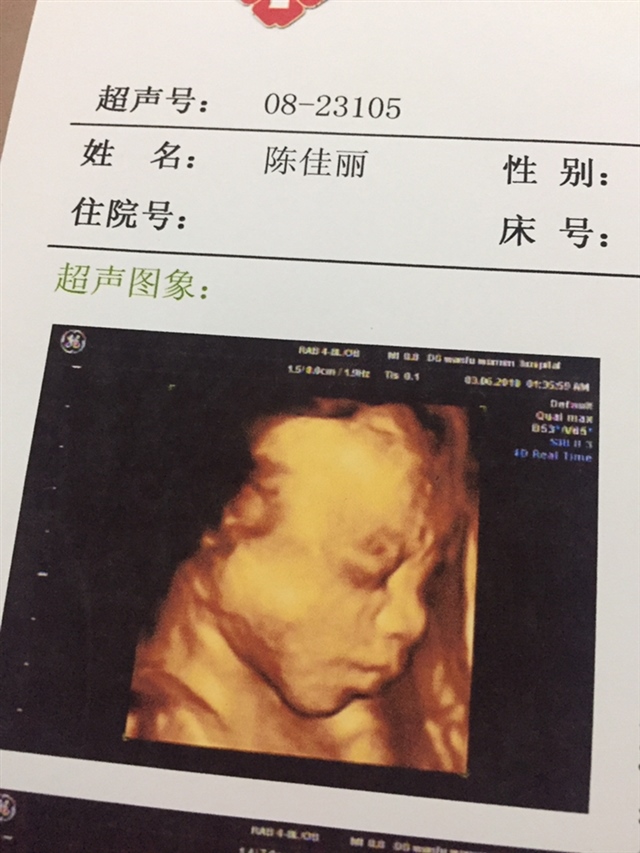

A陳家👑大小姐[帖主]:我22周才约上的,25 5天的时候去查的

接大排畸顺利通过

A陳家👑大小姐[帖主]:是的,我在深圳预约不到,老公的姐姐在万福有熟人帮我预约上的

接四维顺利通过